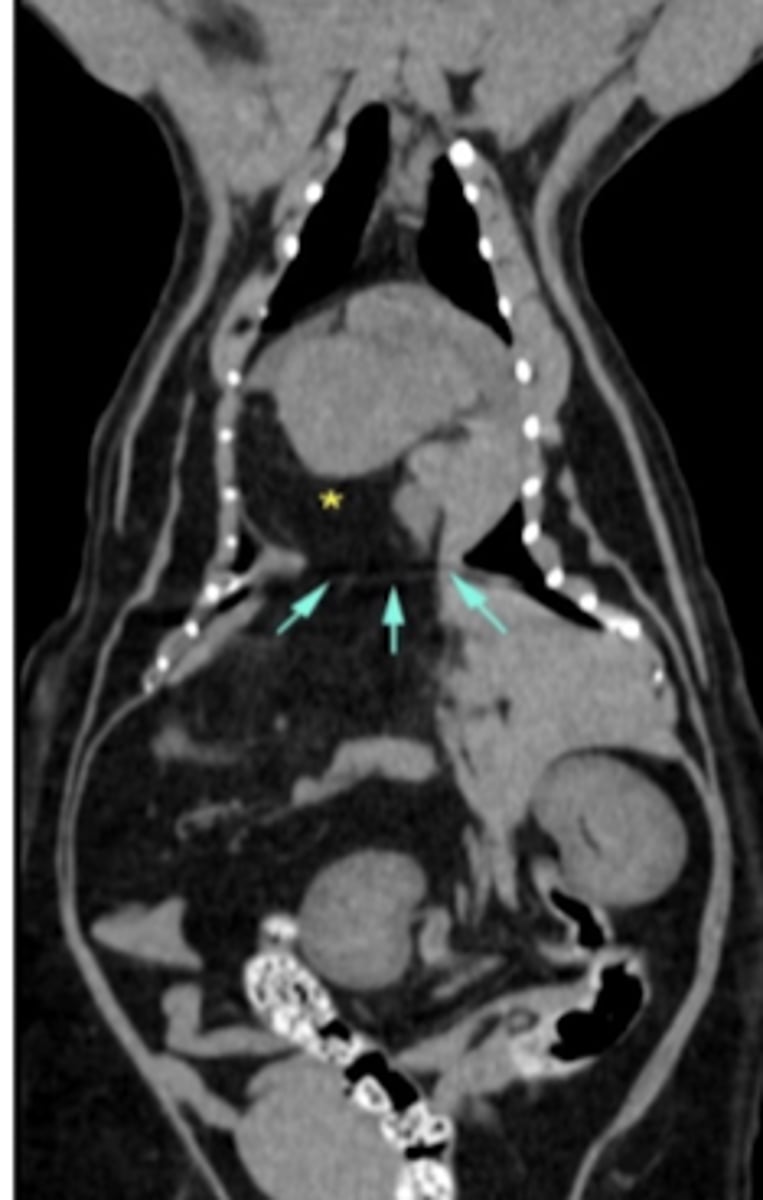

computed tomography (CT)

computed tomography (CT)

what diagnostic imaging technique was used to create this image?

computed tomography (CT)

what diagnostic imaging technique was used to create these images?

computed tomography (CT)

what diagnostic imaging technique was used to create this image?

radiology

ultrasound

CT- most useful

MRI

if we want to assess the respiratory tract, what imaging techniques are the best?